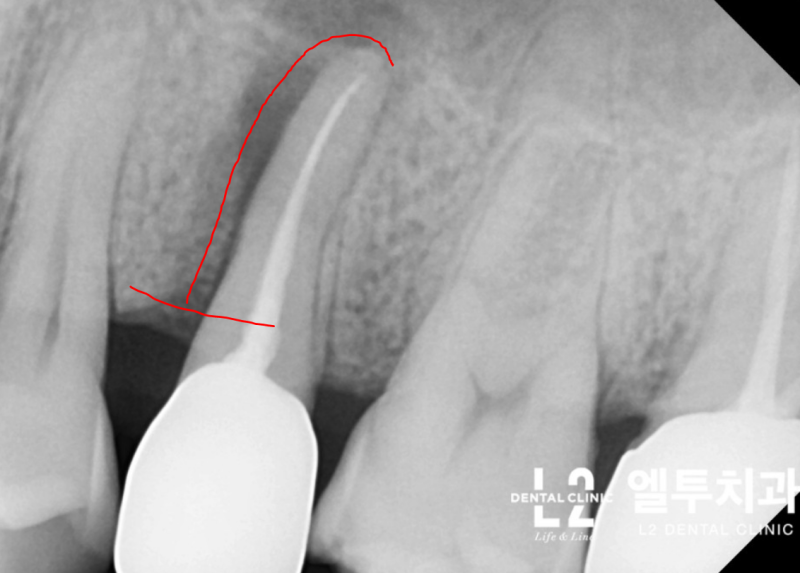

큰어금니와 작은어금니의 갈라진 치아 모습에는 차이가 있는데, 큰어금니의 갈라진 치아는 대부분 “기능적 팁” 쪽, 즉 치아에서 더 큰 스트레스를 받는 부분에서 발생합니다. (아래 포스팅 참조) https://blog.naver.com/sunnyflow/222654941394 Q-ray 촬영으로 어금니 크랙(균열)을 미리 확인하고 대비할 수 있습니다. 닥터&치주과의사 최순호 입니다 오늘은 어금니 중문으로 가는데… blog.naver.com 물론 기능교두의 기능교두는 작은 어금니에도 크랙이 생기는 경우가 많은데, 치아가 부러지는 원인. 음식을 씹을 때 위아래로 씹지 말고 나란히 씹는다. 이것을 치과 용어로 “Lateral Guidance”라고 하는데 위 사진에서 색종이(교합용지)를 찍으면 치아에 가해지는 힘이 화살표 방향으로 퍼지는 것을 볼 수 있습니다. 다시 케이스로 돌아가서 왼쪽 위 어금니가 이전에 근관치료와 크라운 치료를 받았고 씹을 때 불편하다고 하셨습니다. X-레이를 보면 치근/크라운 치료를 받은 어금니 주변에 어두운 그림자가 보일 것입니다. 뼈가 녹으면서 “J자 모양”이 되고 X-레이에서 보이는 이러한 방사선학적 변화는 종종 치아의 깊은 층에 균열이 있음을 나타냅니다(크라운 뿌리 균열, 뿌리 균열 = 치근. 갈라진 치아). 측방 구강 내부에서 송곳니가 곧게 연마되는 것과 같이 측면 안내 중에 치아가 강한 측면 힘을 받는 것으로 추론할 수 있습니다. 이 힘이 계속되면서 작은 어금니 부위에도 깊은 균열이 발생했다. 이 정도까지 치아 사이의 간격이 벌어지면 치과에서 치료할 방법이 없기 때문에 발치 후 임플란트 치료를 권해드립니다. 발치 모습. 화살표가 가리키는 부분을 자세히 보면 치아의 머리 부분에서 시작하여 치근 깊숙이 뻗어나가는 크랙(균열)을 볼 수 있습니다. 입 안의 세균이 미세하게 새는 것은 균열선을 따라서만 진행될 수 있어 잇몸뼈가 재흡수되어 씹을 때 통증이 발생합니다. 임플란트 수술은 발치 당일에 시행하고 일정 기간 치유 후 작은 어금니 부위에 임플란트 크라운을 식립합니다. 이러한 현상을 가진 환자들은 이상한 점을 발견할 수 있는데, 반대측 치아에서도 비슷한 상황을 관찰하는 경우가 매우 흔하다. 반대쪽 소구치를 보면 잇몸뼈가 주변 치아와는 매우 다른 방식으로 흡수되는 것을 볼 수 있습니다. 이 치아 역시 치근 치료와 크라운 치료를 한 치아이기 때문에 치아의 치근쪽에 크랙이 나타난 것으로 의심됩니다. 문제 치아 옆의 작은 어금니도 균열이 의심되는 Q-선 형광 검사에서 관찰되었습니다. 금이 간 치아가 강하게 의심되었지만 어쨌든 심각한 치은 골 흡수가 관찰되었으므로 “진단”+ “치료”의 목적으로 치은 박리를 시행했습니다. (환자분들이 아프지 않을때까지 보관하라고 하셔서 알고 있습니다.) 이렇게 입에 금이 간 치아가 많은 분들은 예방적 크라운 치료를 권해드리고 있습니다. 크라운 치료는 앞니의 단점이 있지만 “치아 보호”가 최우선입니다. 위에서 언급한 2개의 치아 외에도 양쪽 소구치에 크랙이 관찰되어 더 진행하면 바로 발치할 수 있어 환자에게 크라운 치료를 알리고 진행하였다. 너무 늦기 전에… 깨진 치아를 무시하면 종종 손을 사용하지 않고 발치 및 임플란트 치료가 발생할 수 있습니다. https://blog.naver.com/sunnyflow/222413456775 치아가 깨지거나 부러져 부주의로 발치를 하게 된 사례 안녕하세요. L2치과의원장 최순하오 원장입니다. 최근 치과에 다녀온 환자에서… blog.naver.com 바로 씹어도 통증이 없어도… 상당한 크랙이 관찰된다면 예방적 크라운 치료를 고려해보시는 것을 강력히 추천드립니다:) 오늘의 기사가 도착합니다. 끝. 스마트폰에서 위 부분을 터치하시면 다이얼로 전환됩니다.서울시 강남구 봉은사로 469, S-TOWER L2, 4층 치과